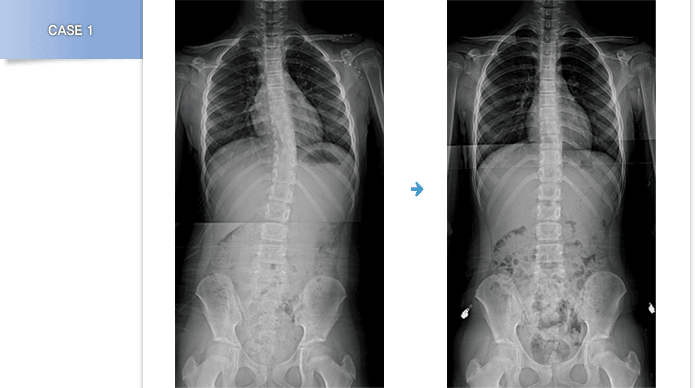

자세로 인한 유연성 척추측만증일 경우 조기에 교정하지 않으면 나이가 들면서 점점 더 진행될 수 있습니다.

따라서 발, 다리에 문제가 있다면 반드시 척추 X-ray를 찍어보는 것이 좋습니다.

자세관련 척추측만증이 다리 길이의 차이나 골반 부정렬로 발생하였다면

발보조기나 신발치료를 통해 교정이 가능합니다.

또한 자세의 문제를 해결하기 위해서는 운동치료와 자세교정이 병행되어야

효과적입니다. |